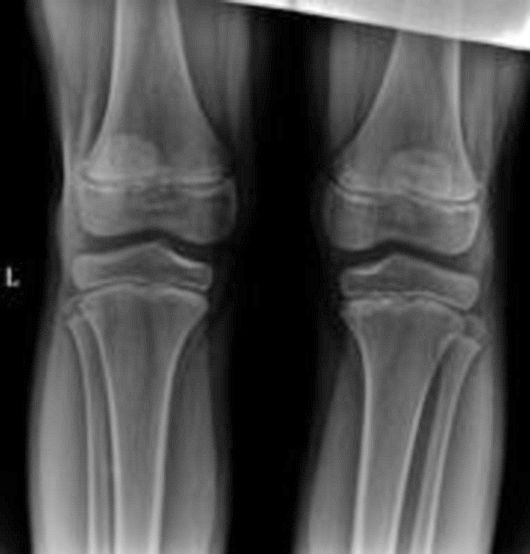

m 11 右下肢痛1 月

双侧对比未见明确异常。其疼痛可能为生长痛。